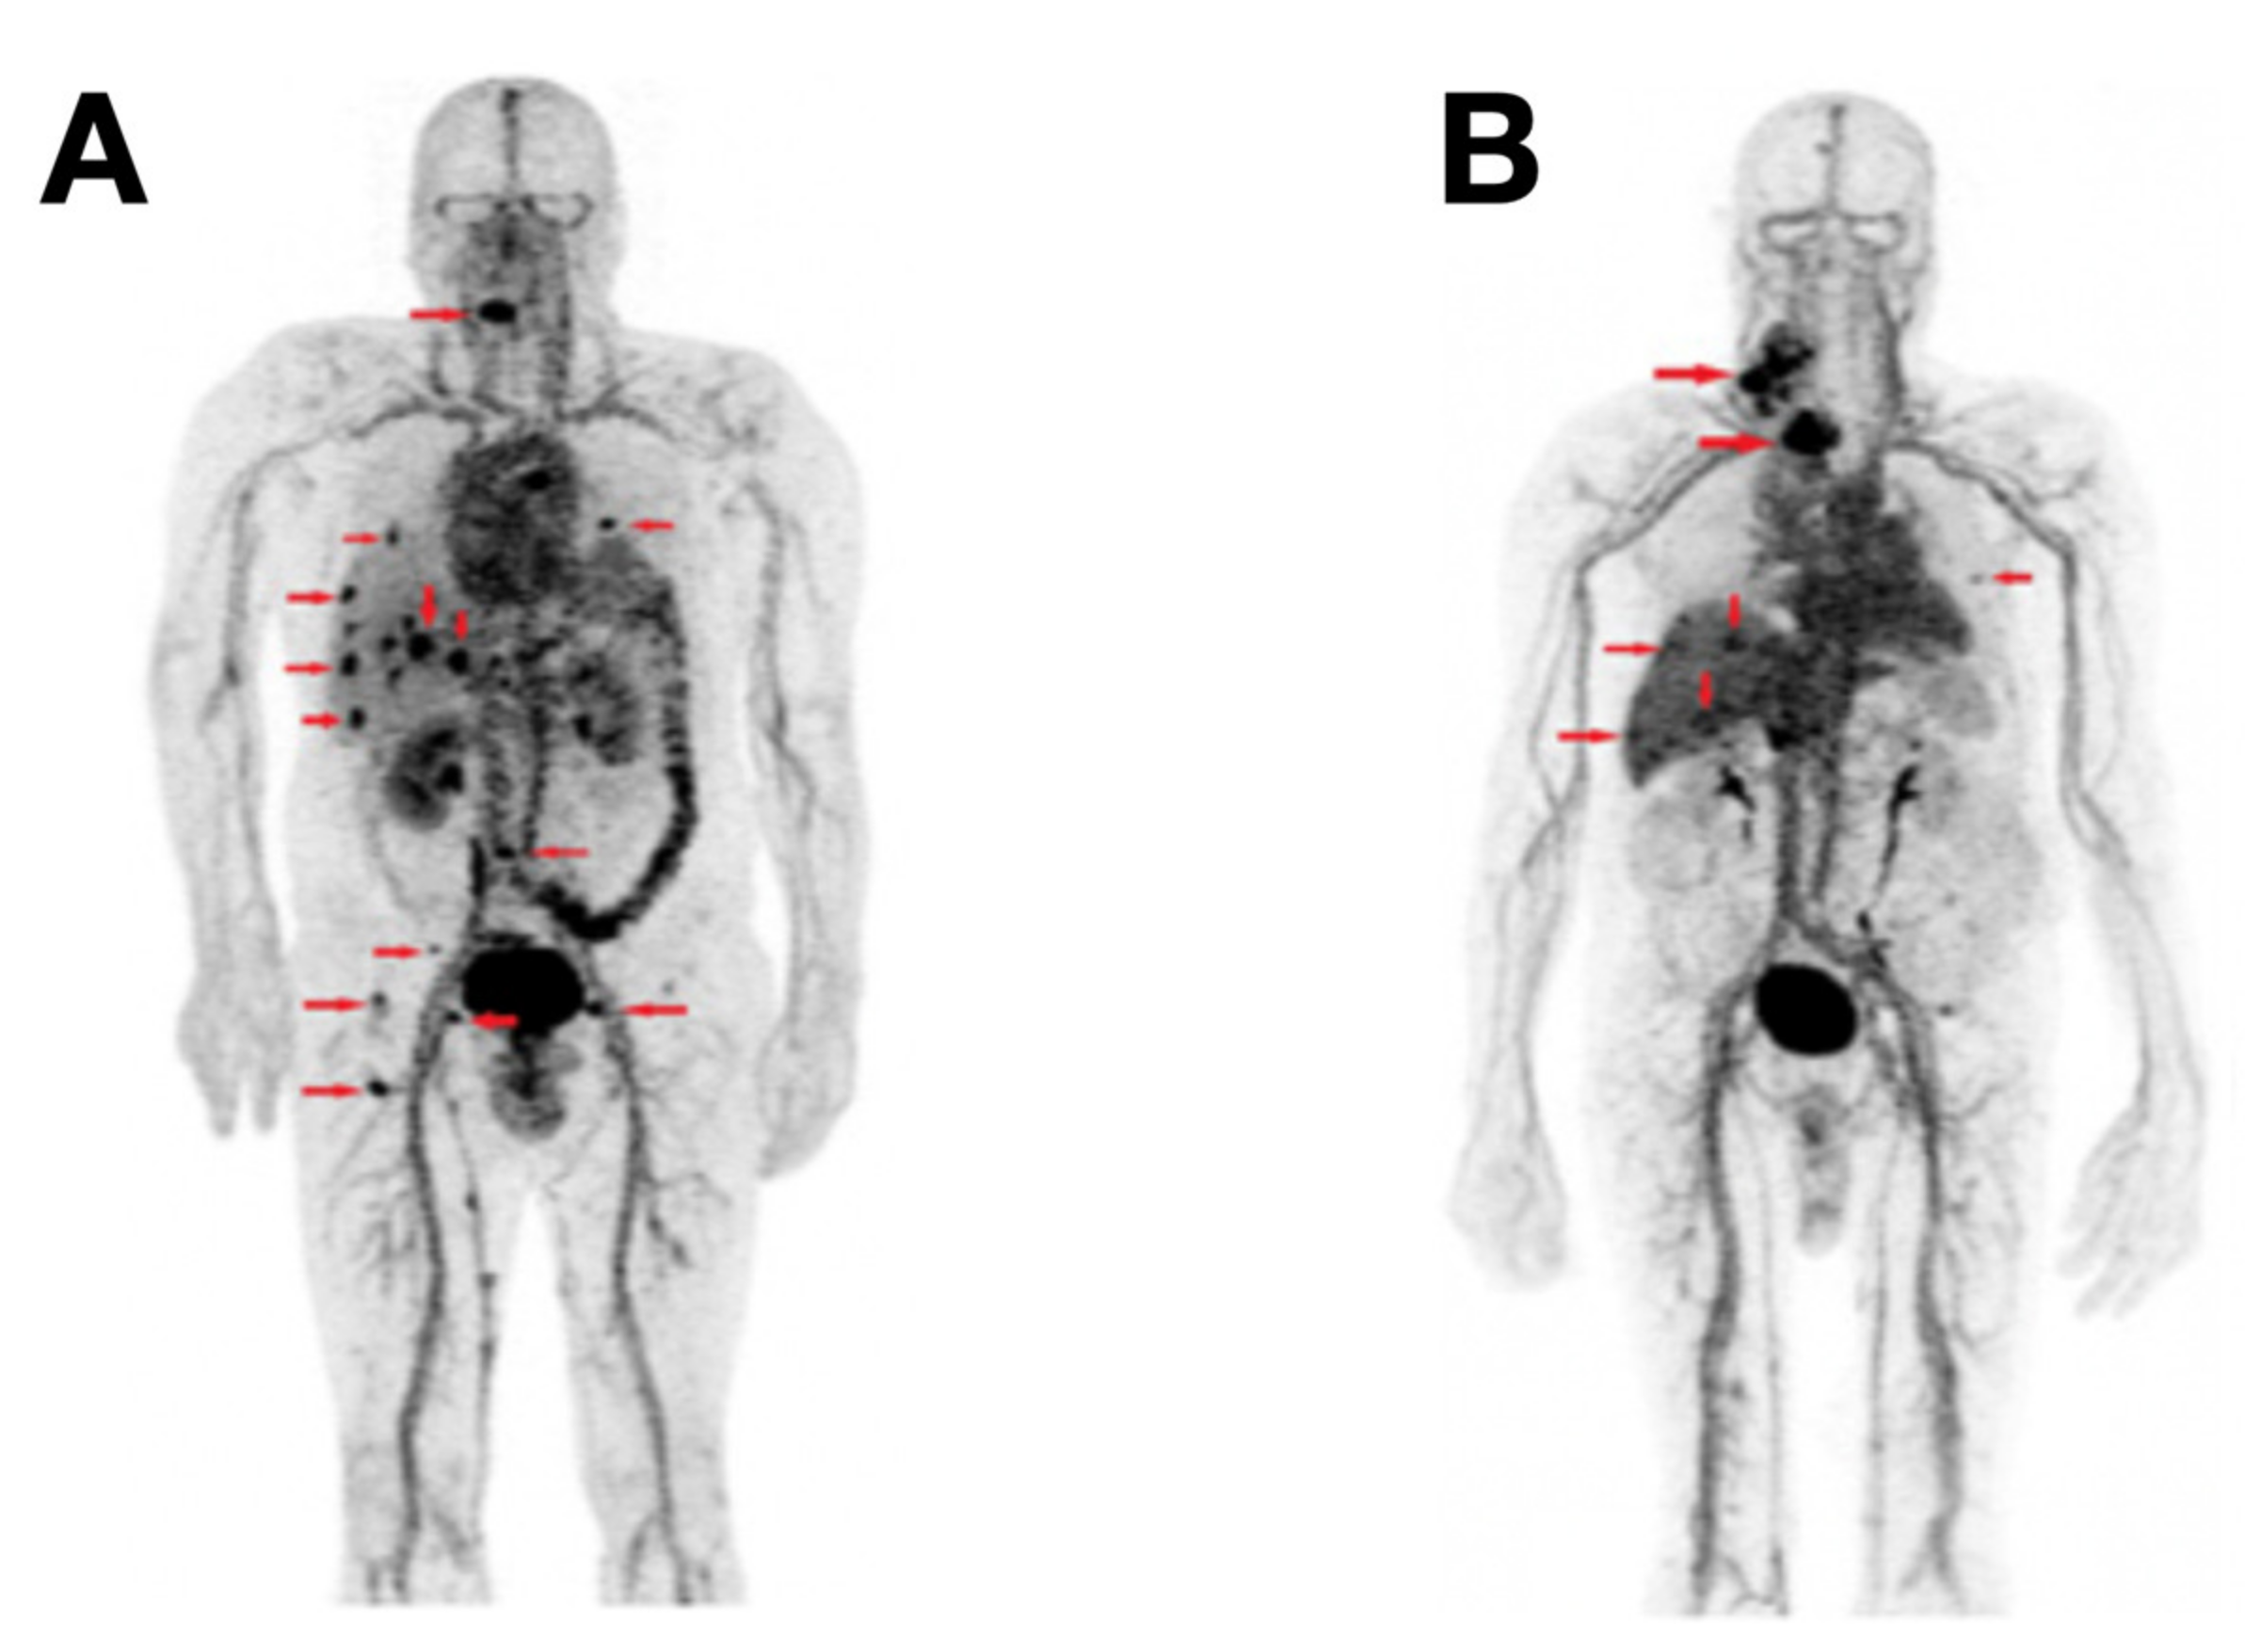

- Ho, A.L.; Grewal, R.K.; Leboeuf, R.; Sherman, E.J.; Pfister, D.G.; Deandreis, D.; Pentlow, K.S.; Zanzonico, P.B.; Haque, S.; Gavane, S.; et al. Selumetinib-Enhanced Radioiodine Uptake in Advanced Thyroid Cancer. N. Engl. J. Med. 2013, 368, 623–632. [Google Scholar] [CrossRef]

- Dunn, L.A.; Sherman, E.J.; Baxi, S.S.; Tchekmedyian, V.; Grewal, R.K.; Larson, S.M.; Pentlow, K.S.; Haque, S.; Tuttle, R.M.; Sabra, M.M.; et al. Vemurafenib Redifferentiation of BRAF Mutant, RAI-Refractory Thyroid Cancers. J. Clin. Endocrinol. Metab. 2018, 104, 1417–1428. [Google Scholar] [CrossRef]